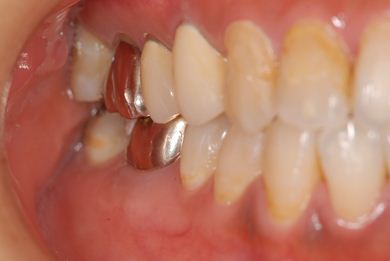

抜歯即日スピードインプラント治療

| 性別/年齢 | 女性 / 39歳 | ||||||||||||||||||||||||||||||||

| 主訴 | 左前歯の虫歯治療を希望。 | ||||||||||||||||||||||||||||||||

| 治療内容 | インプラント1本(抜歯即日スピードインプラント)、メタルボンドセラミック1本 | ||||||||||||||||||||||||||||||||

| 総治療費 | 458,588円 | ||||||||||||||||||||||||||||||||

| 治療期間 | 1年0ヶ月 |